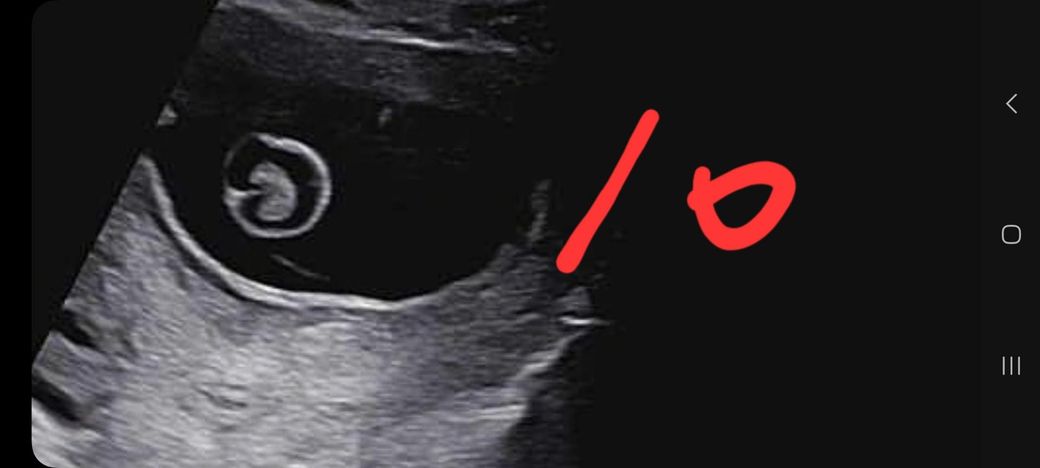

임신 12주차 태아 뇌 초음파 좀 봐주세요ㅜ

임신 12주차 이며 10주차 때 뇌 모양이 신경쓰인다고

앞쪽(이마 쪽)이 신경 쓰인다며 소견서 써줄테니

대학병원 다녀와보라 하시네요ㅜ

(10주차 사진은 10이라 적었습니다.)

• 2번 째 사진